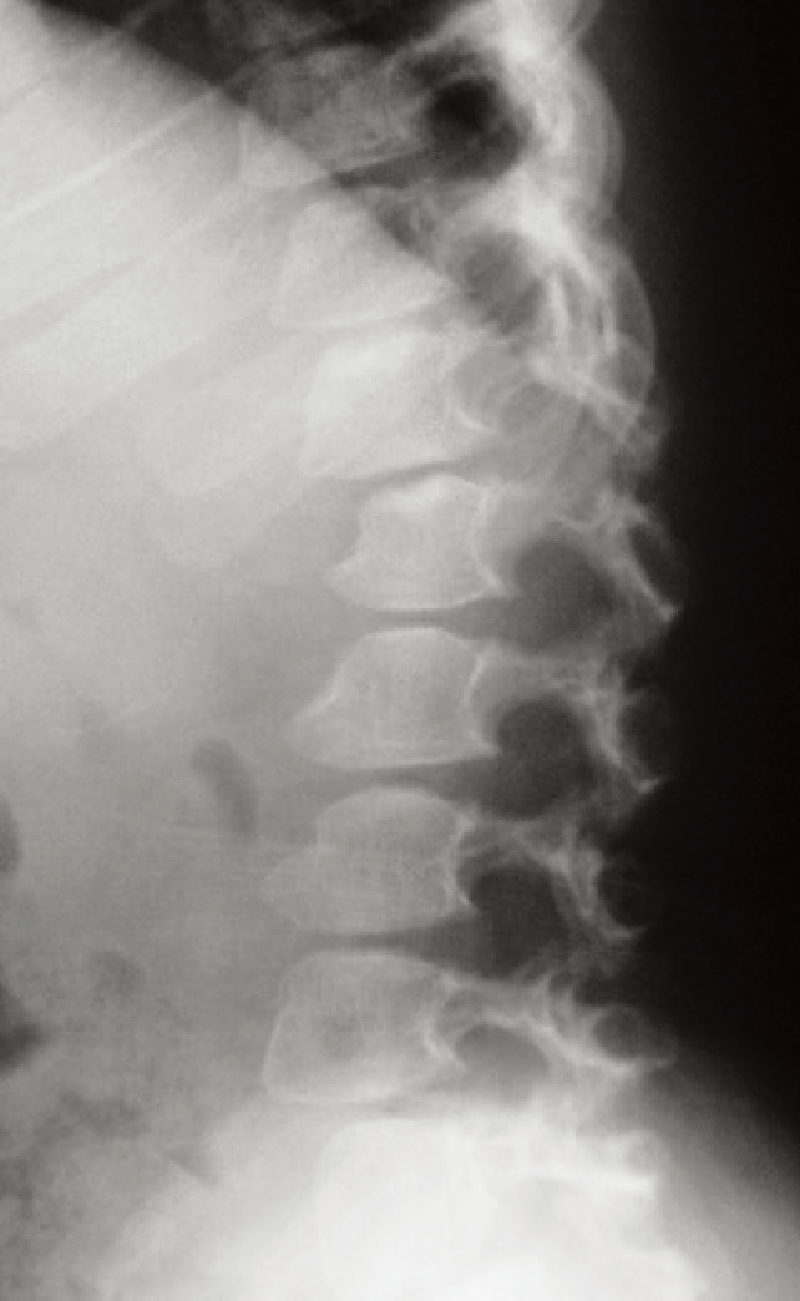

特徴的な画像所見:腰椎の前弯がみられる。扁平椎で椎体の前方舌状突出像(anterior tongue)が特徴的である(A)。

A. 脊椎側面像(2歳5カ月、女):椎体前方の舌状突出を伴った扁平椎が特徴的である。

手指の短管骨は著しく短く、指節骨が弾丸状(bullet shaped)である。長管骨では骨端が小さく、骨幹端は幅が広い(B)。

B. 両下肢正面像(2歳5カ月、女):骨端は小さく、骨幹端は幅が広い。

AとBは同じ症例。

椎体前方の舌状突出はモルキオ症候群に類似する。

四肢短縮型低身長であること、顔貌正常で骨格系以外の合併症が少ないことなどがムコ多糖症とは異なる。